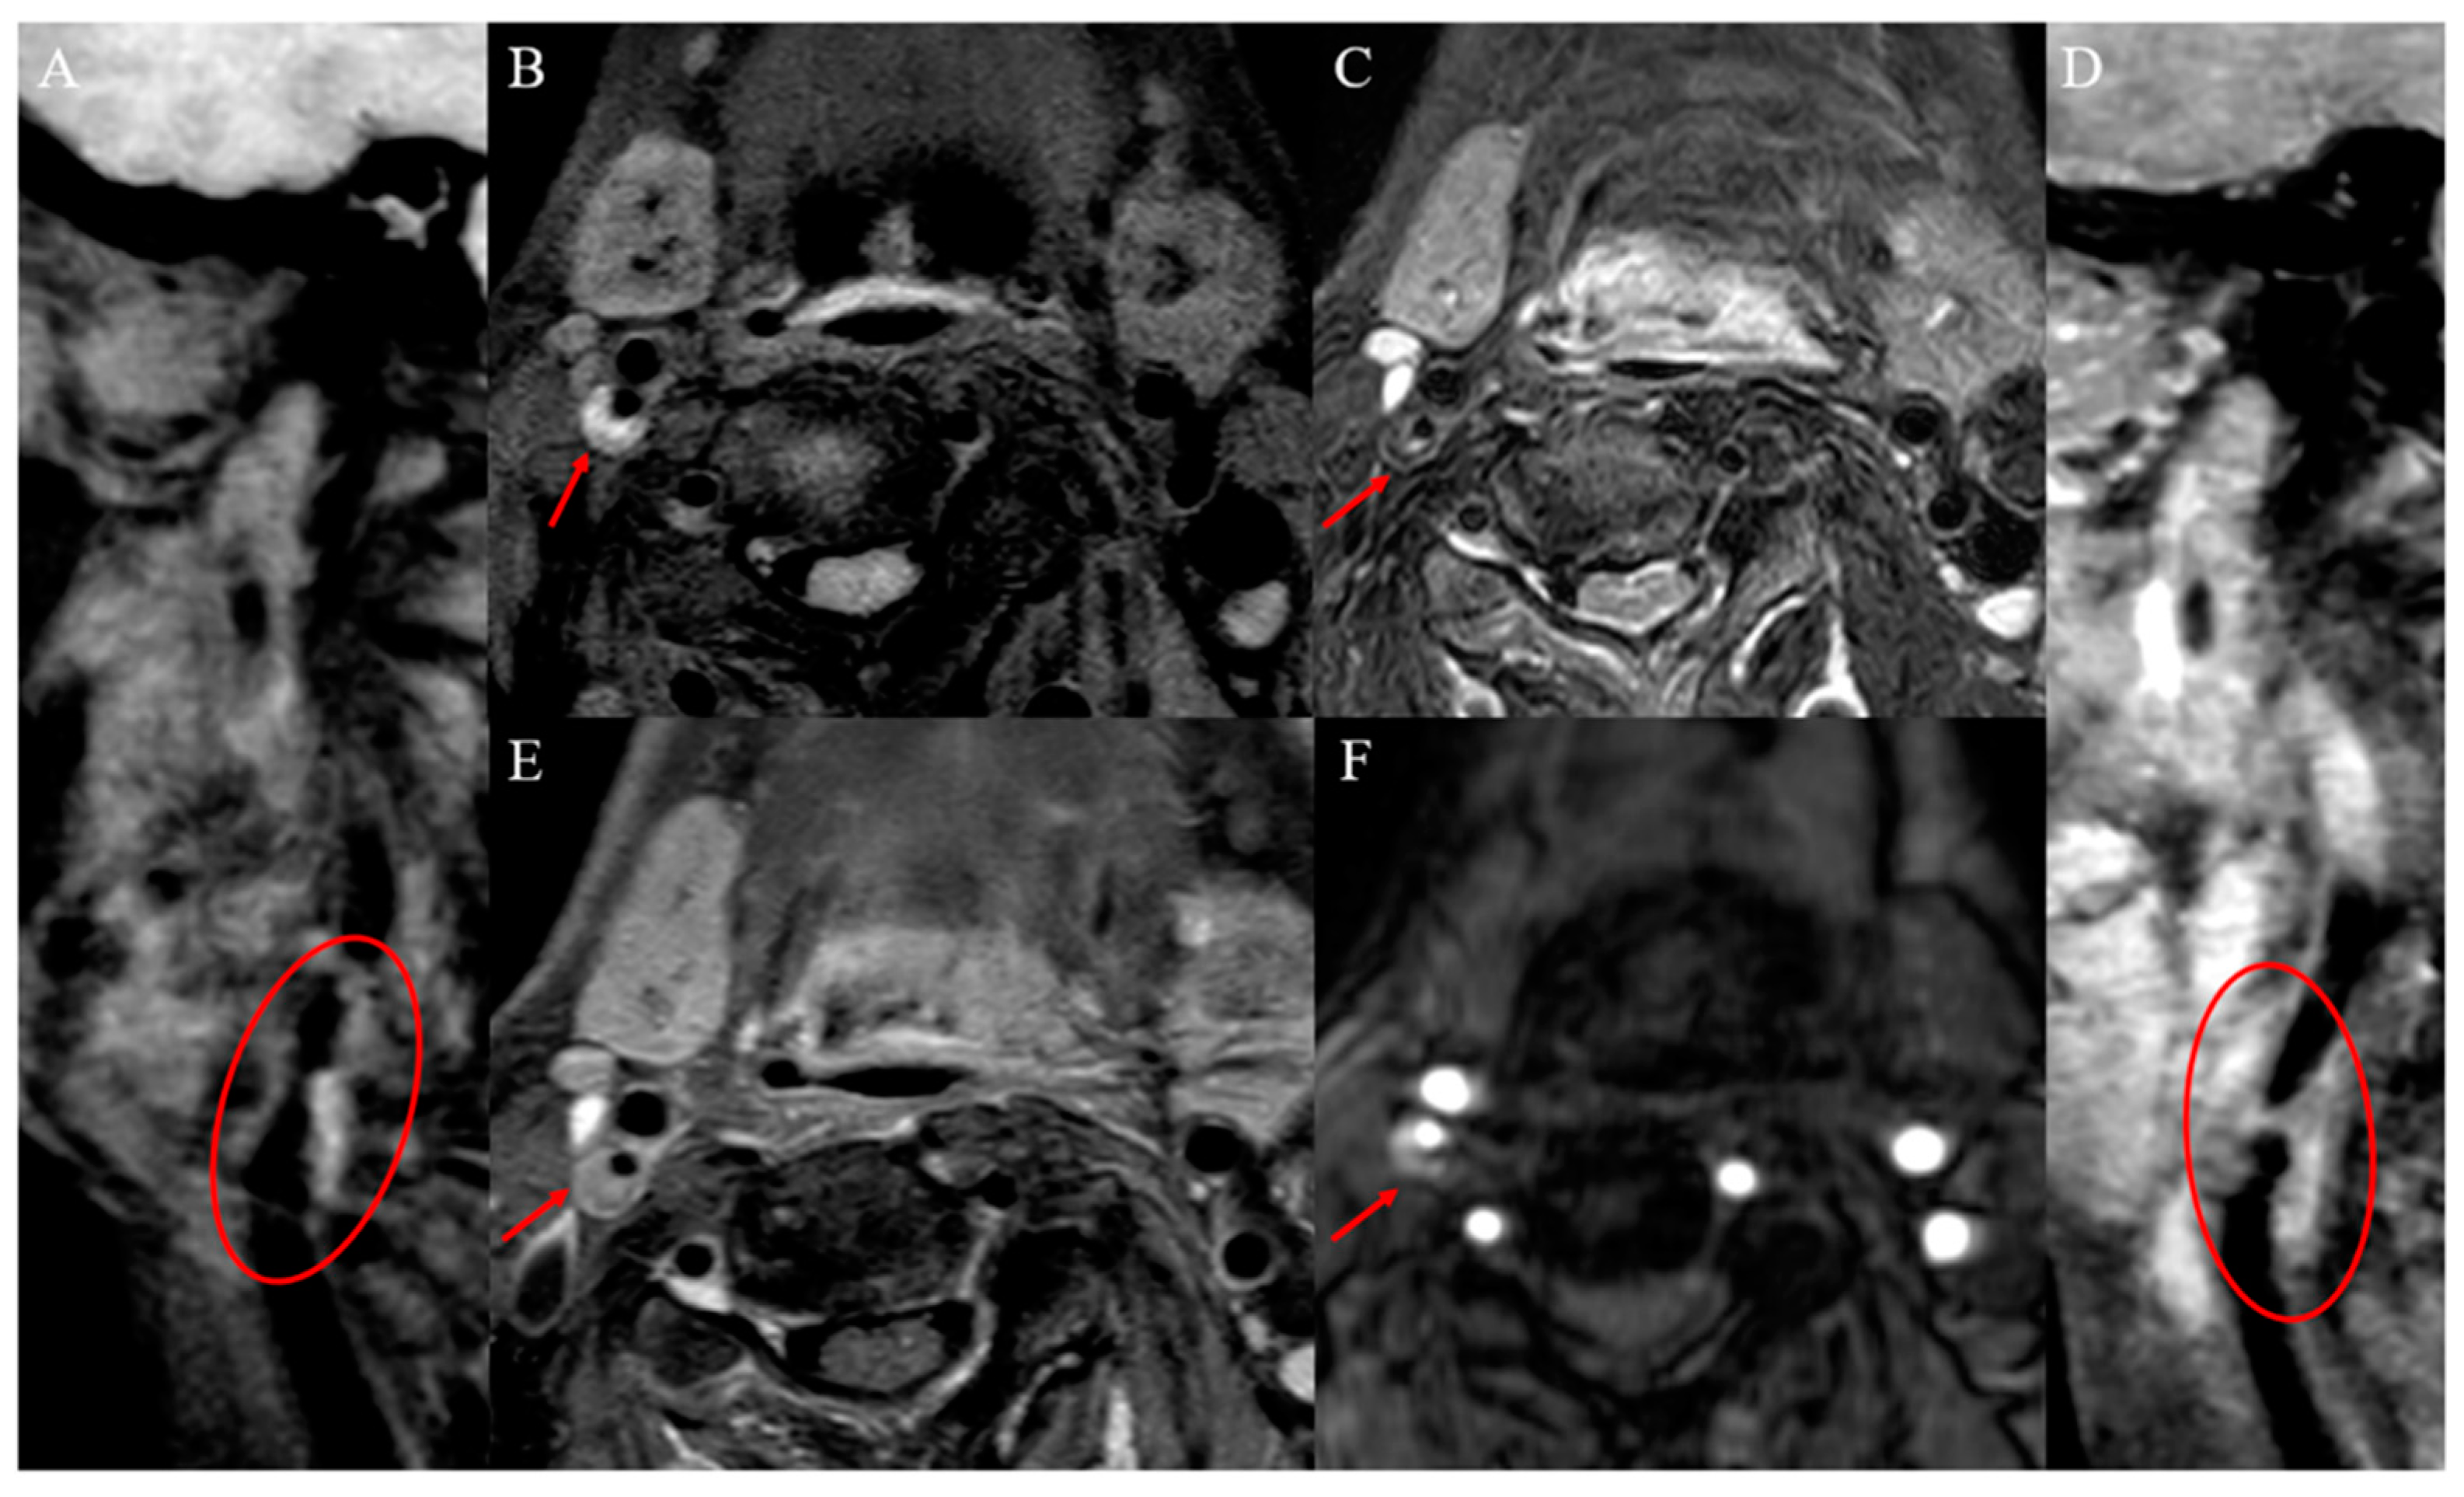

2.1.2. Intraplaque Hemorrhage

2.1.3. Intraplaque Inflammation and Neovascularization